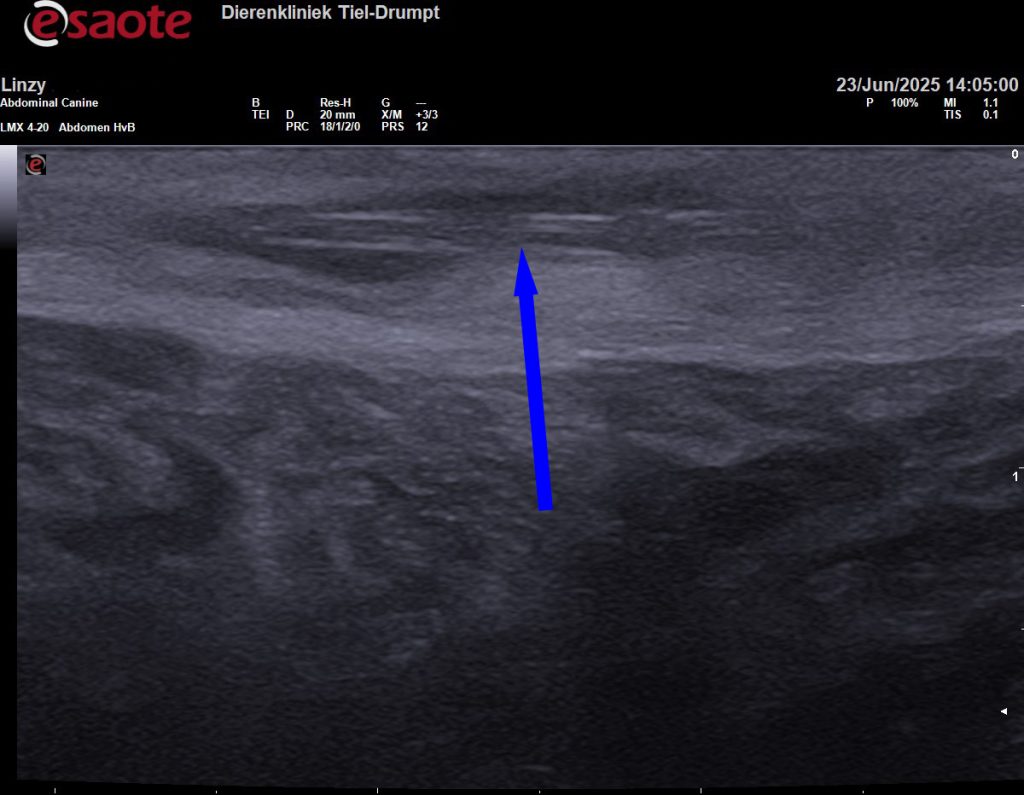

Grasaren kunnen ook op andere plaatsen voorkomen, zoals tussen de tenen of op willekeurige plekken onder de huid. Onderstaande echobeeld is van een grasaar die op een dijbeen van een hond onder de huid was “gekropen”.